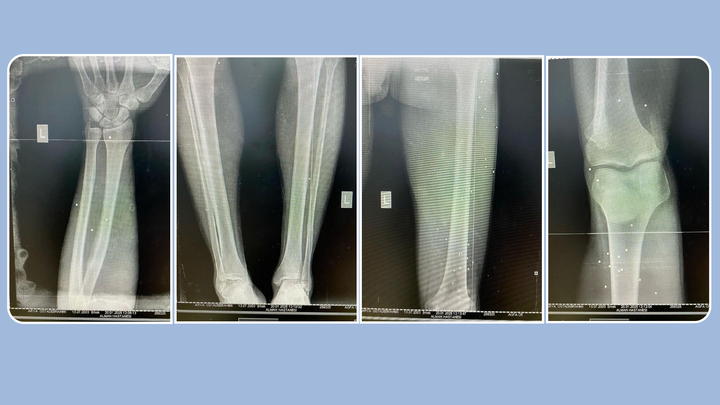

از شلیک بیش از صد گلوله در پنجم آبان، پزشک داوطلب توانست تنها حدود ۳۰ ساچمه را از بدنش خارج کند. با این حال، بیش از ۸۰ ساچمه هنوز در بدن او باقی ماندهاند. نتیجه معاینات پزشکی در ترکیه نیز این موضوع را تایید کرده است و گفتهاند بسیاری از ساچمهها در عمق بافتها فرو رفتهاند.

در اثر این وضعیت، آریا هنوز هم با درد مزمن دستوپنجه نرم میکند. پای چپش میلنگد، زیرا یکی از ساچمهها در استخوان پا فرو رفته و بدون تجهیزات جراحی پیشرفته، خارج کردن آن ممکن نیست. پزشکان ترکیهای پس از بررسیهای دقیق هشدار دادهاند که جراحی برای خارج کردن بقیه ساچمهها میتواند بسیار خطرناک باشد؛ چون شماری از آنها در نواحی حساسی مانند اطراف رگهای ساعد دست چپ، پشت زانو، محل خم شدن پا و کشاله ران چپ قرار دارند.

نبود امکانات جراحی پیشرفته و هزینههای سنگین عمل در ترکیه باعث شده تاکنون امکان خارج کردن ساچمهها وجود نداشته باشد. آریا میگوید: «ساچمههایی که به زانوهایم خوردهاند قابل لمساند.»

تصاویر سیتیاسکن از وضعیت ساچمههای شلیک شده به بدن آریا استادابراهیمی؛